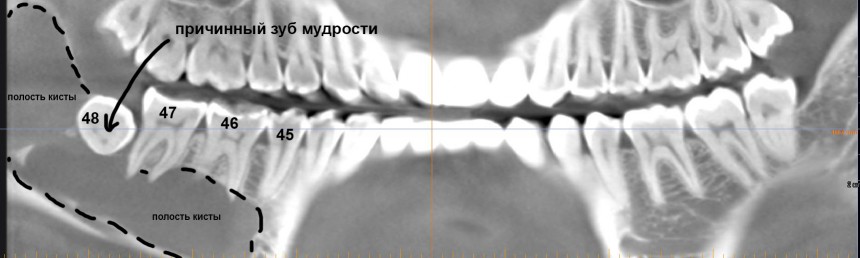

Но самое неприятное, что можно ждать от ретинированных зубов мудрости — это кисты.

Их источником является фолликул, окружающий зачаток зуба. Когда зуб прорезывается, фолликул исчезает, но в случае ретенции он сохраняется и может служить источником опухолей и кист.

Иногда — достаточно больших и весьма опасных для здоровья.

И хотя всё это вполне себе лечится, согласитесь, что лучше не доводить себя до такого состояния.

- Ретинированный (непрорезавшийся) зуб мудрости. Вроде как, не беспокоит. Находится где-то там, далеко. В жевании не участвует и никогда участвовать не будет. К чему может привести ретинированная восьмёрка, мы с вами уже знаем. Имеет ли смысл ждать этих осложнений? Мне думается, что нет, не имеет.